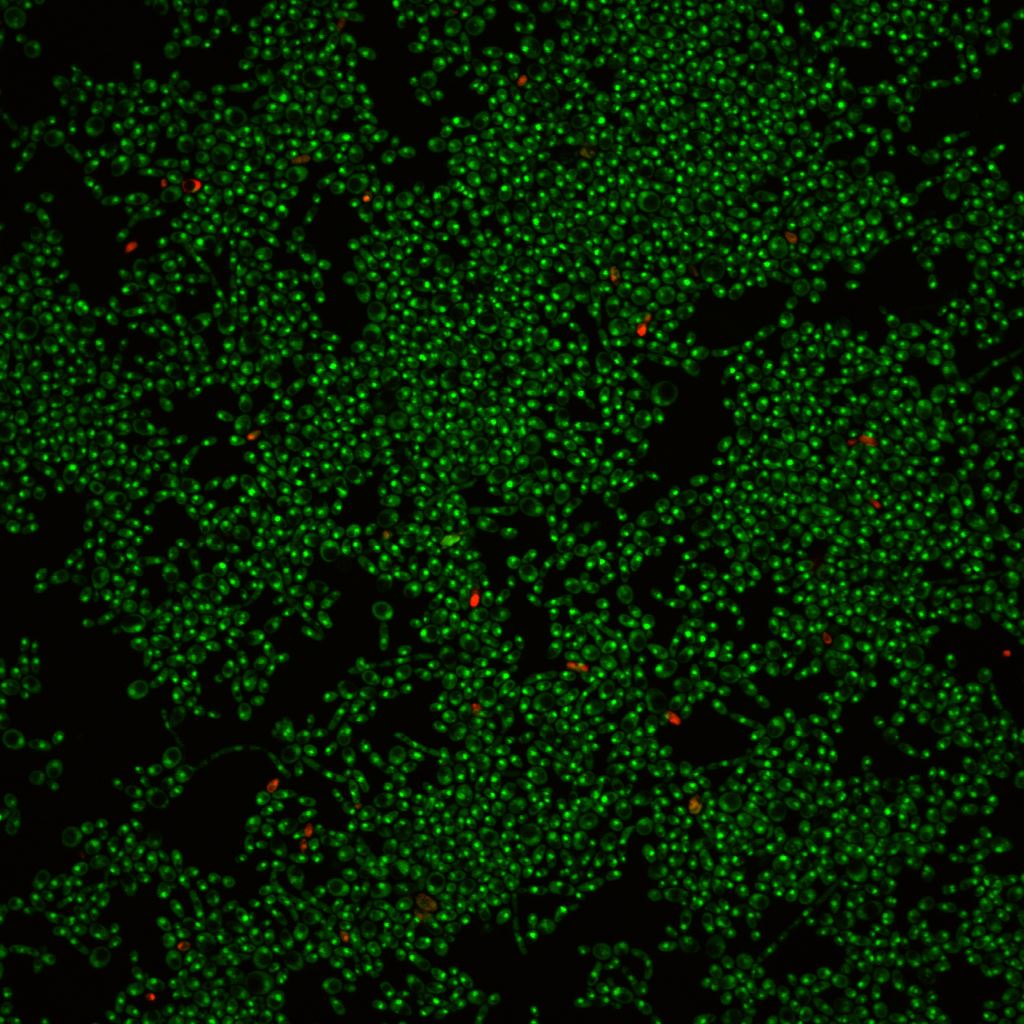

Confocal laser scanning microscopy shows that C. albicans develops biofilms on a plastic surface (left photo), and addition of purpurin suppresses biofilm formation (right photo). Green cells are living and red cells are dead.

The ability of C. albicans to grow in filament form and develop into biofilms on a plastic surface (left photo) is blocked by the addition of purpurin (right photo).